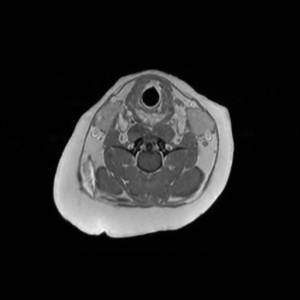

Main Gallery

Playing with a photo gallery function. It is possible to have multiple galleries, each within a namespace.